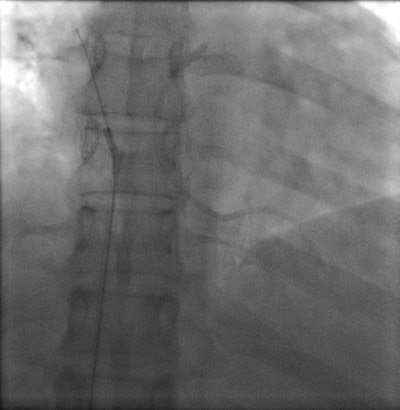

Chest radiograph of a 32-year-old woman shows cardiac migration of the proximal fragment of a fractured portacath. All images courtesy of Drs. Jamal Al Deen Alkoteesh and Maysam T. Abu Sa'a.The portacath fracture was incidentally discovered on chest radiograph, which showed cardiac migration of the proximal fragment. Echocardiography was performed and showed preserved left ventricular function with ejection fraction of about 50% to 55%. No regional wall motion abnormalities seen. Linear shadow was seen on echocardiography, representing the retained fragment.

Percutaneous retrieval of the retained fragment of the fractured portacath catheter was successfully accomplished on the second attempt. Following prepping of the right groin, the right femoral vein was punctured and an 8 French sheath was inserted. Selective catheterization of the right ventricle was performed using a 6 French catheter. A 25-mm snare was used to capture the migrated retained fragment. It was then removed successfully without immediate complications.